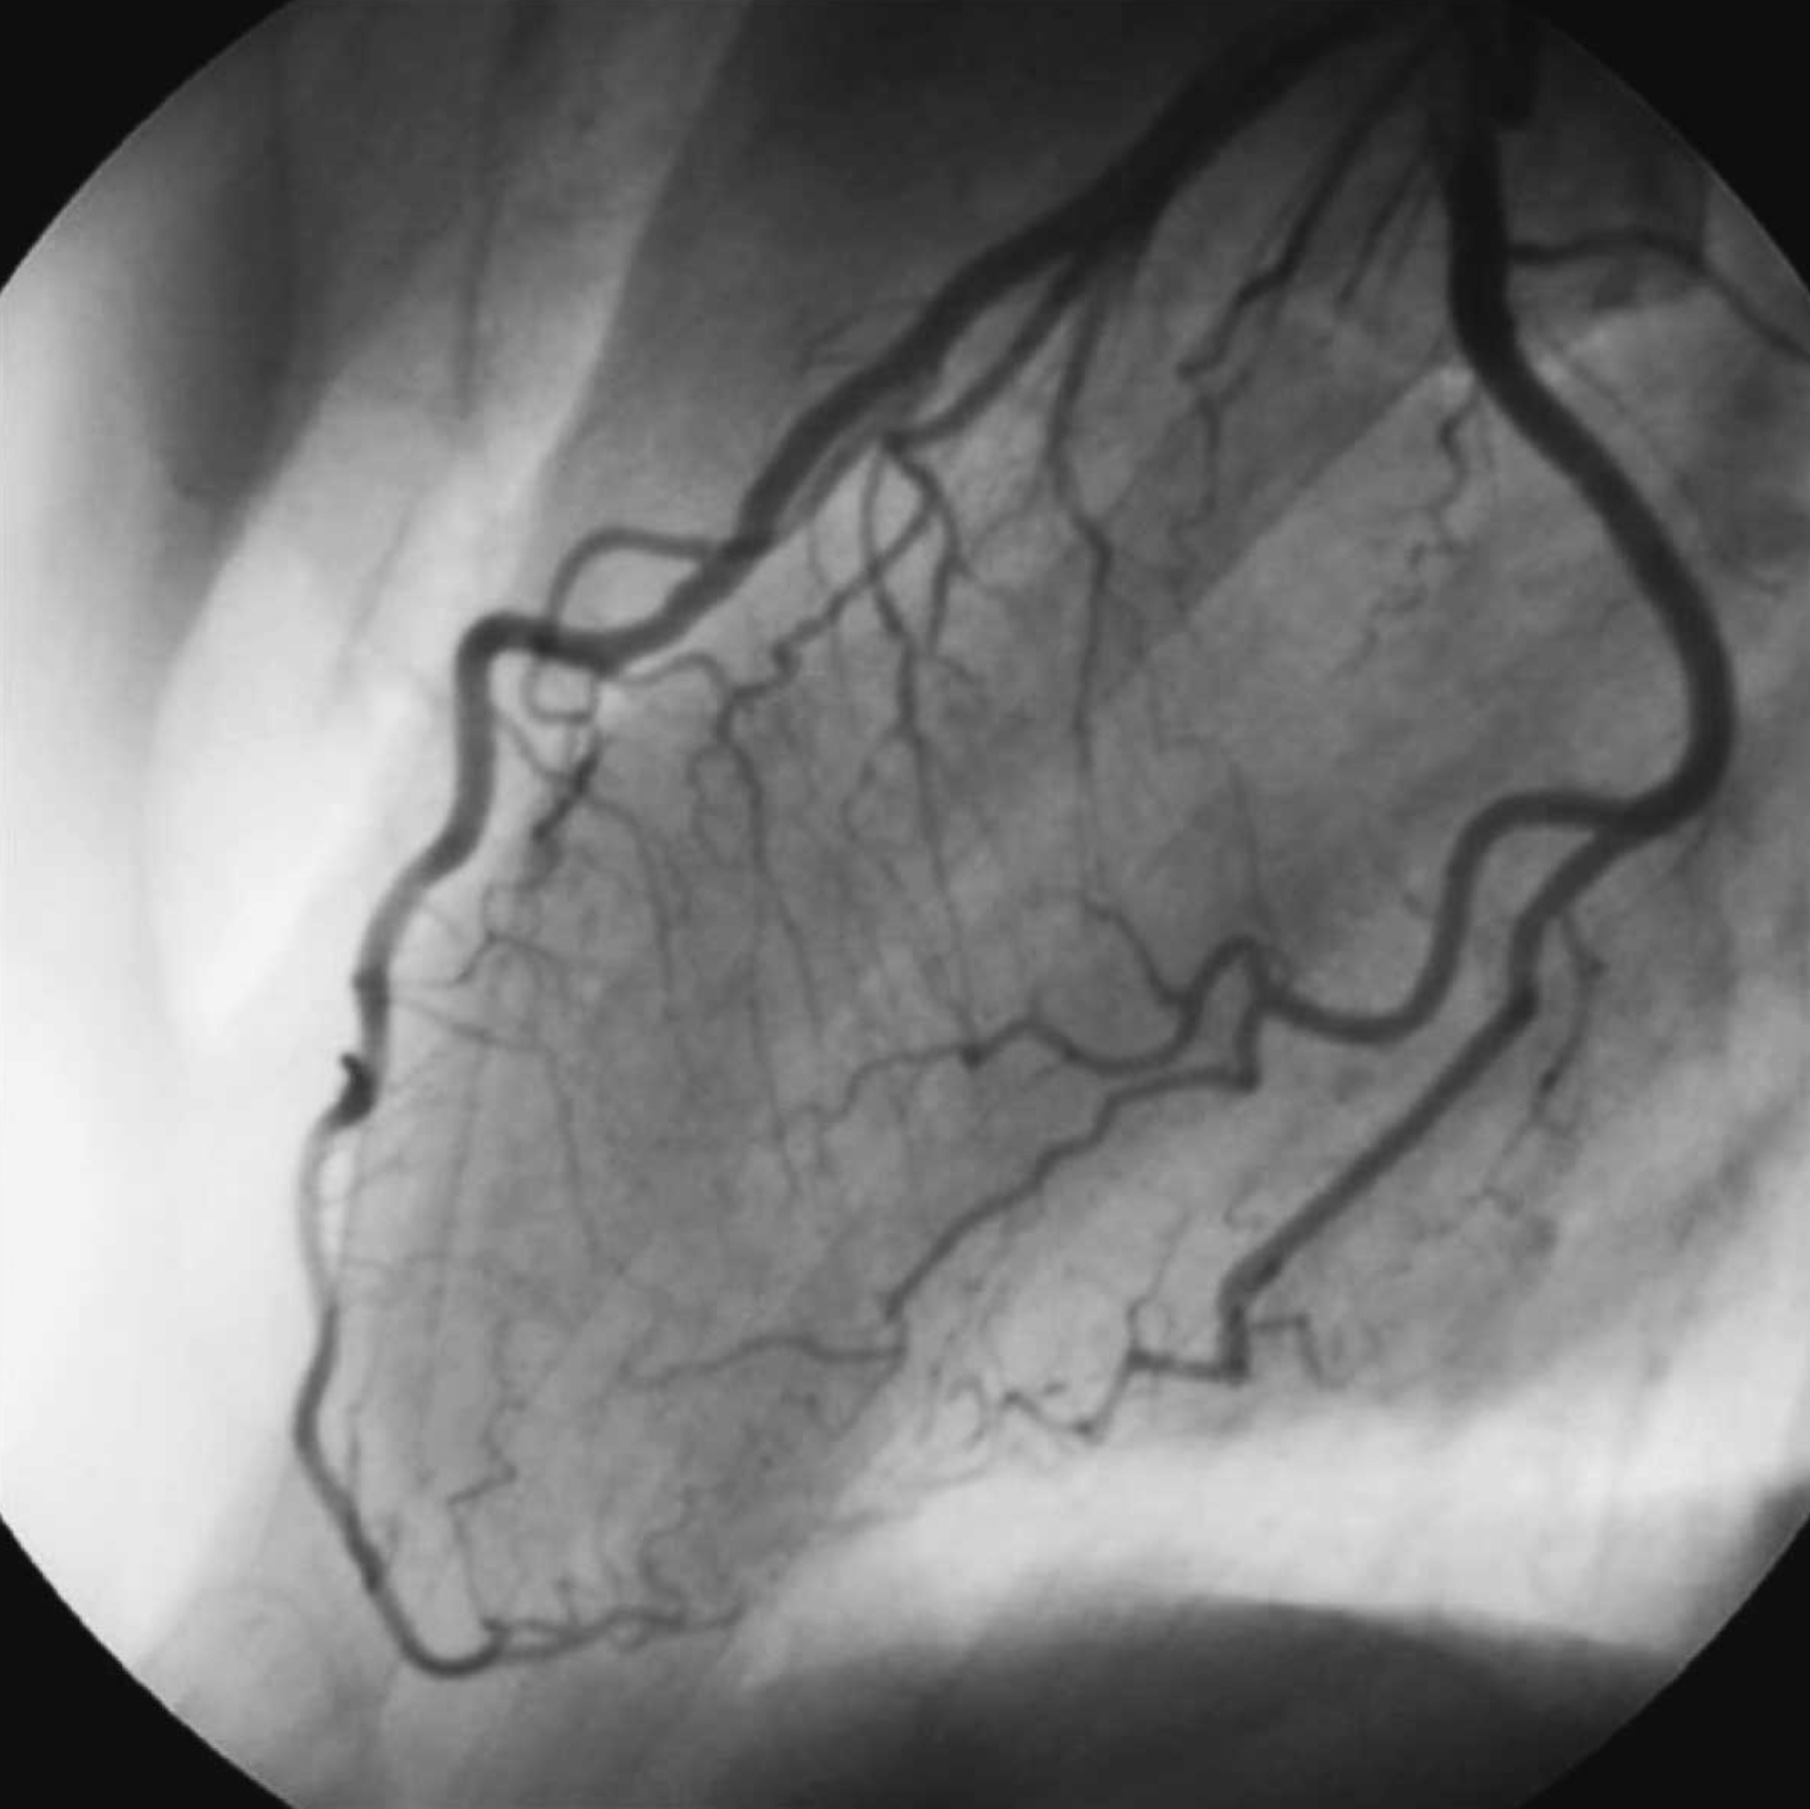

1. An 63 year old man has a heart arrhythmia. Upon further investigation, an angiogram shows an occlusion of the proximal right coronary artery. Why would this potentially cause arrhythmia? Discuss the anatomy and relationships of the right coronary artery and branches as well as the complementary venous drainage. Include mention of any commonly seen anatomical variances, if any.

2. A patient is shown to have a partial occlusion of their anterior interventricular artery (left anterior descending artery). Discuss the anatomy and relationships of the left coronary artery and branches as well as the complementary venous drainage. Why is an occlusion in this artery especially dangerous and what potential surgical solutions can be used as treatment? Include mention of commonly seen anatomical variances, if any.

4. The left coronary artery gives rise to the anterior interventricular artery and this artery, in turn, supplies the anterior two thirds of the interventricular septum (widow maker). (True)

5. Left or right dominance of the heart is determined by whether the right or the left coronary artery supplies the posterior interventricular artery. (True)

6. Blockage of the right coronary artery proximal to the sinuatrial branch indicates the need to implant a pacemaker. (True)